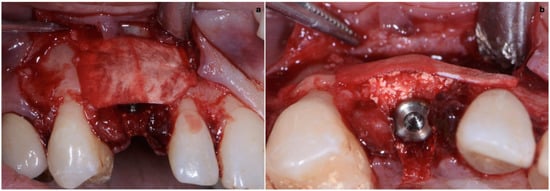

The implant site was prepared in a fully guided manner, using drills of progressively larger diameter, so that at the moment of guided implant insertion, the fixture could reach the pre-established position with enough primary stability to consent immediate provisionalization (35 Ncm) (Figure 6a,b). The implant shoulder should be palatal with respect to the imaginary line that connects the buccal profile of the adjacent teeth without placing it so that it is excessively palatal, in order to avoid creating prosthetic emergence profiles that are too horizontal, which are difficult to maintain in terms of hygiene.

Figure 6. (a,b) Implant placement after guided preparation of implant site.